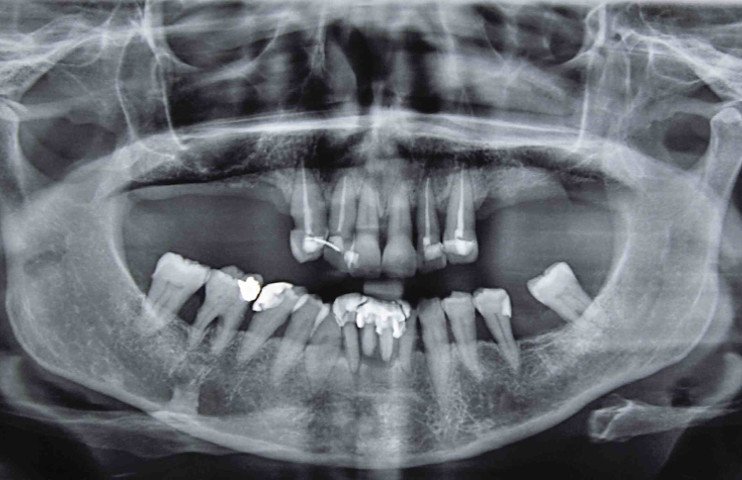

Ортопантомограмма представляет собой обзорный круговой рентгеновский снимок. На нем челюсть представлена полностью и развернута в плоскости.

Несомненным преимуществом методики является возможность оценить не только состояние зубов (в т. ч. корневых каналов), но и близлежащих структур – челюстных костей, придаточных пазух и т. д.

Ортопантомограмма зубов представляет собой панорамный рентгеновский снимок, который позволяет получить полное изображение зубочелюстной системы пациента. Врачи отмечают, что этот метод диагностики является незаменимым инструментом для выявления различных заболеваний, таких как кариес, парадонтит, а также для планирования ортодонтического лечения и имплантации. Показания к проведению ортопантомограммы включают наличие зубной боли, необходимость оценки состояния зубов перед хирургическими вмешательствами и контроль после лечения. Однако у данного метода есть и противопоказания. Врачи предостерегают от его использования у беременных женщин и пациентов с повышенной чувствительностью к радиации. Важно помнить, что решение о проведении ортопантомограммы должно приниматься врачом на основании индивидуальных показаний и состояния здоровья пациента.

Ортопантомограмма (ОПГ) — это рентгеновский снимок, который позволяет получить общее изображение всех зубов, челюстей и окружающих тканей. Этот метод диагностики широко используется в стоматологии для выявления различных заболеваний, таких как кариес, парадонтит, а также для оценки состояния зубных рядов перед установкой имплантов или ортодонтическим лечением. Показания к проведению ОПГ включают планирование лечения, контроль за динамикой заболеваний и диагностику аномалий развития. Однако у процедуры есть и противопоказания: это беременность, наличие тяжелых заболеваний, связанных с облучением, и аллергия на контрастные вещества, если они используются. Важно помнить, что ОПГ — это безопасный и информативный метод, который помогает стоматологам принимать обоснованные решения о лечении.

Ортопантомограмма – рентгеновский снимок, позволяющий провести первичное исследование общего состояния зубов, височно-нижнечелюстных суставов, костной ткани челюстей и гайморовых пазух.

По сравнению с традиционным рентгеновским аппаратом ортопантомограф дает пониженную лучевую нагрузку, поэтому его безбоязненно можно использовать при возникновении необходимости в панорамном снимке. На ортопантомограмме видны зубы, челюстно-лицевые суставы, кости лицевого отдела черепа, носовые пазухи.